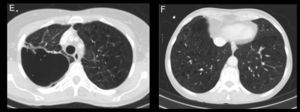

A 57-year-old woman, former smoker, consulted due to irritative cough. Chest radiograph showed a right paratracheal mass and a nodule in the left lower lobe (LLL) with characteristics of malignancy. CT revealed a solid, necrotized mass with peripheral enhancement in the right upper lobe (RUL) (Fig. 1A and C), and another similar subpleural lesion in the LLL (Fig. 1B and D), and pathologically enlarged hilar lymph nodes. All lesions were observed on PET.

(A and C) Axial CT slices in the mediastinal and lung windows, respectively. A solid mass 6cm×4cm with infiltrative margins, containing necrosis, and peripheral enhancement in the posterior segment of the RUL adjacent to the posterior pleura. (B and D) Axial CT slices in the mediastinal and lung windows. Another solid lesion is seen in the LLL, adjacent to the diaphragmatic pleura, with infiltrative contours and less necrosis. (E and F) Axial CT slices in lung window, 6 months after starting bevacizumab treatment. In E, the RUL lesion can be seen to be larger, cavitated and with no solid component, and in F, the solid tumor in the LLL is smaller with lower attenuation than in images B and D.

FNAB was performed in both lesions, and the pathology report found EGFR-mutation negative and ALK-mutation negative lung adenocarcinoma. Treatment was started with taxol–carboplatin–bevacizumab (antiangiogenic), followed by maintenance bevacizumab.

In the follow-up CT, the RUL lesion had increased in size, with cavitation and reduced solid component (Fig. 1E). The LLL tumor and lymphadenopathy had reduced in size and attenuation (Fig. 1F).